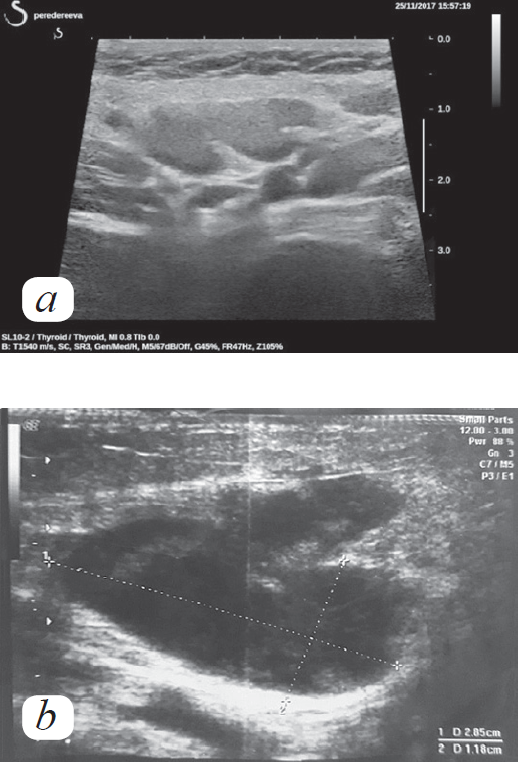

После введения ВВИГ пациент продолжал лихорадить в течение трех дней, сохранялась выраженная лимфаденопатия, отмечено появление шейно-надключичного лимфоузла справа. Выполнено ультразвуковое исследование увеличенных лимфоузлов (рис. 4).

Рис. 4. Ультразвуковые изменения лимфатического узла. a: конгломераты лимфатических узлов — переднешейная группа. Узлы увеличены, дифференцировка снижена, отек окружающих тканей. b: некротически измененный лимфатический узел переднешейной группы. Дифференцировка отсутствует, в режиме цветового доплеровского картирования лимфоузел аваскулярный, контуры неровные. В центре определяются зоны разрежения ткани